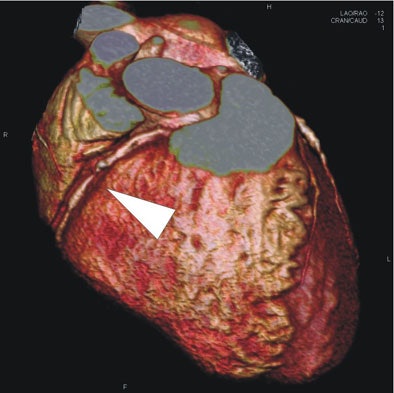

| In a 64-year-old man presenting with chest pain, 3D and multiplanar reconstructions of coronary CTA images show a significant stenosis in the first diagonal branch of the left anterior descending (LAD) artery and a 70% stenosis in the mid right circumflex artery (RCA) (arrows). All images courtesy of Dr. Balázs Ruzsics, Ph.D., and Dr. U. Joseph Schoepf. |